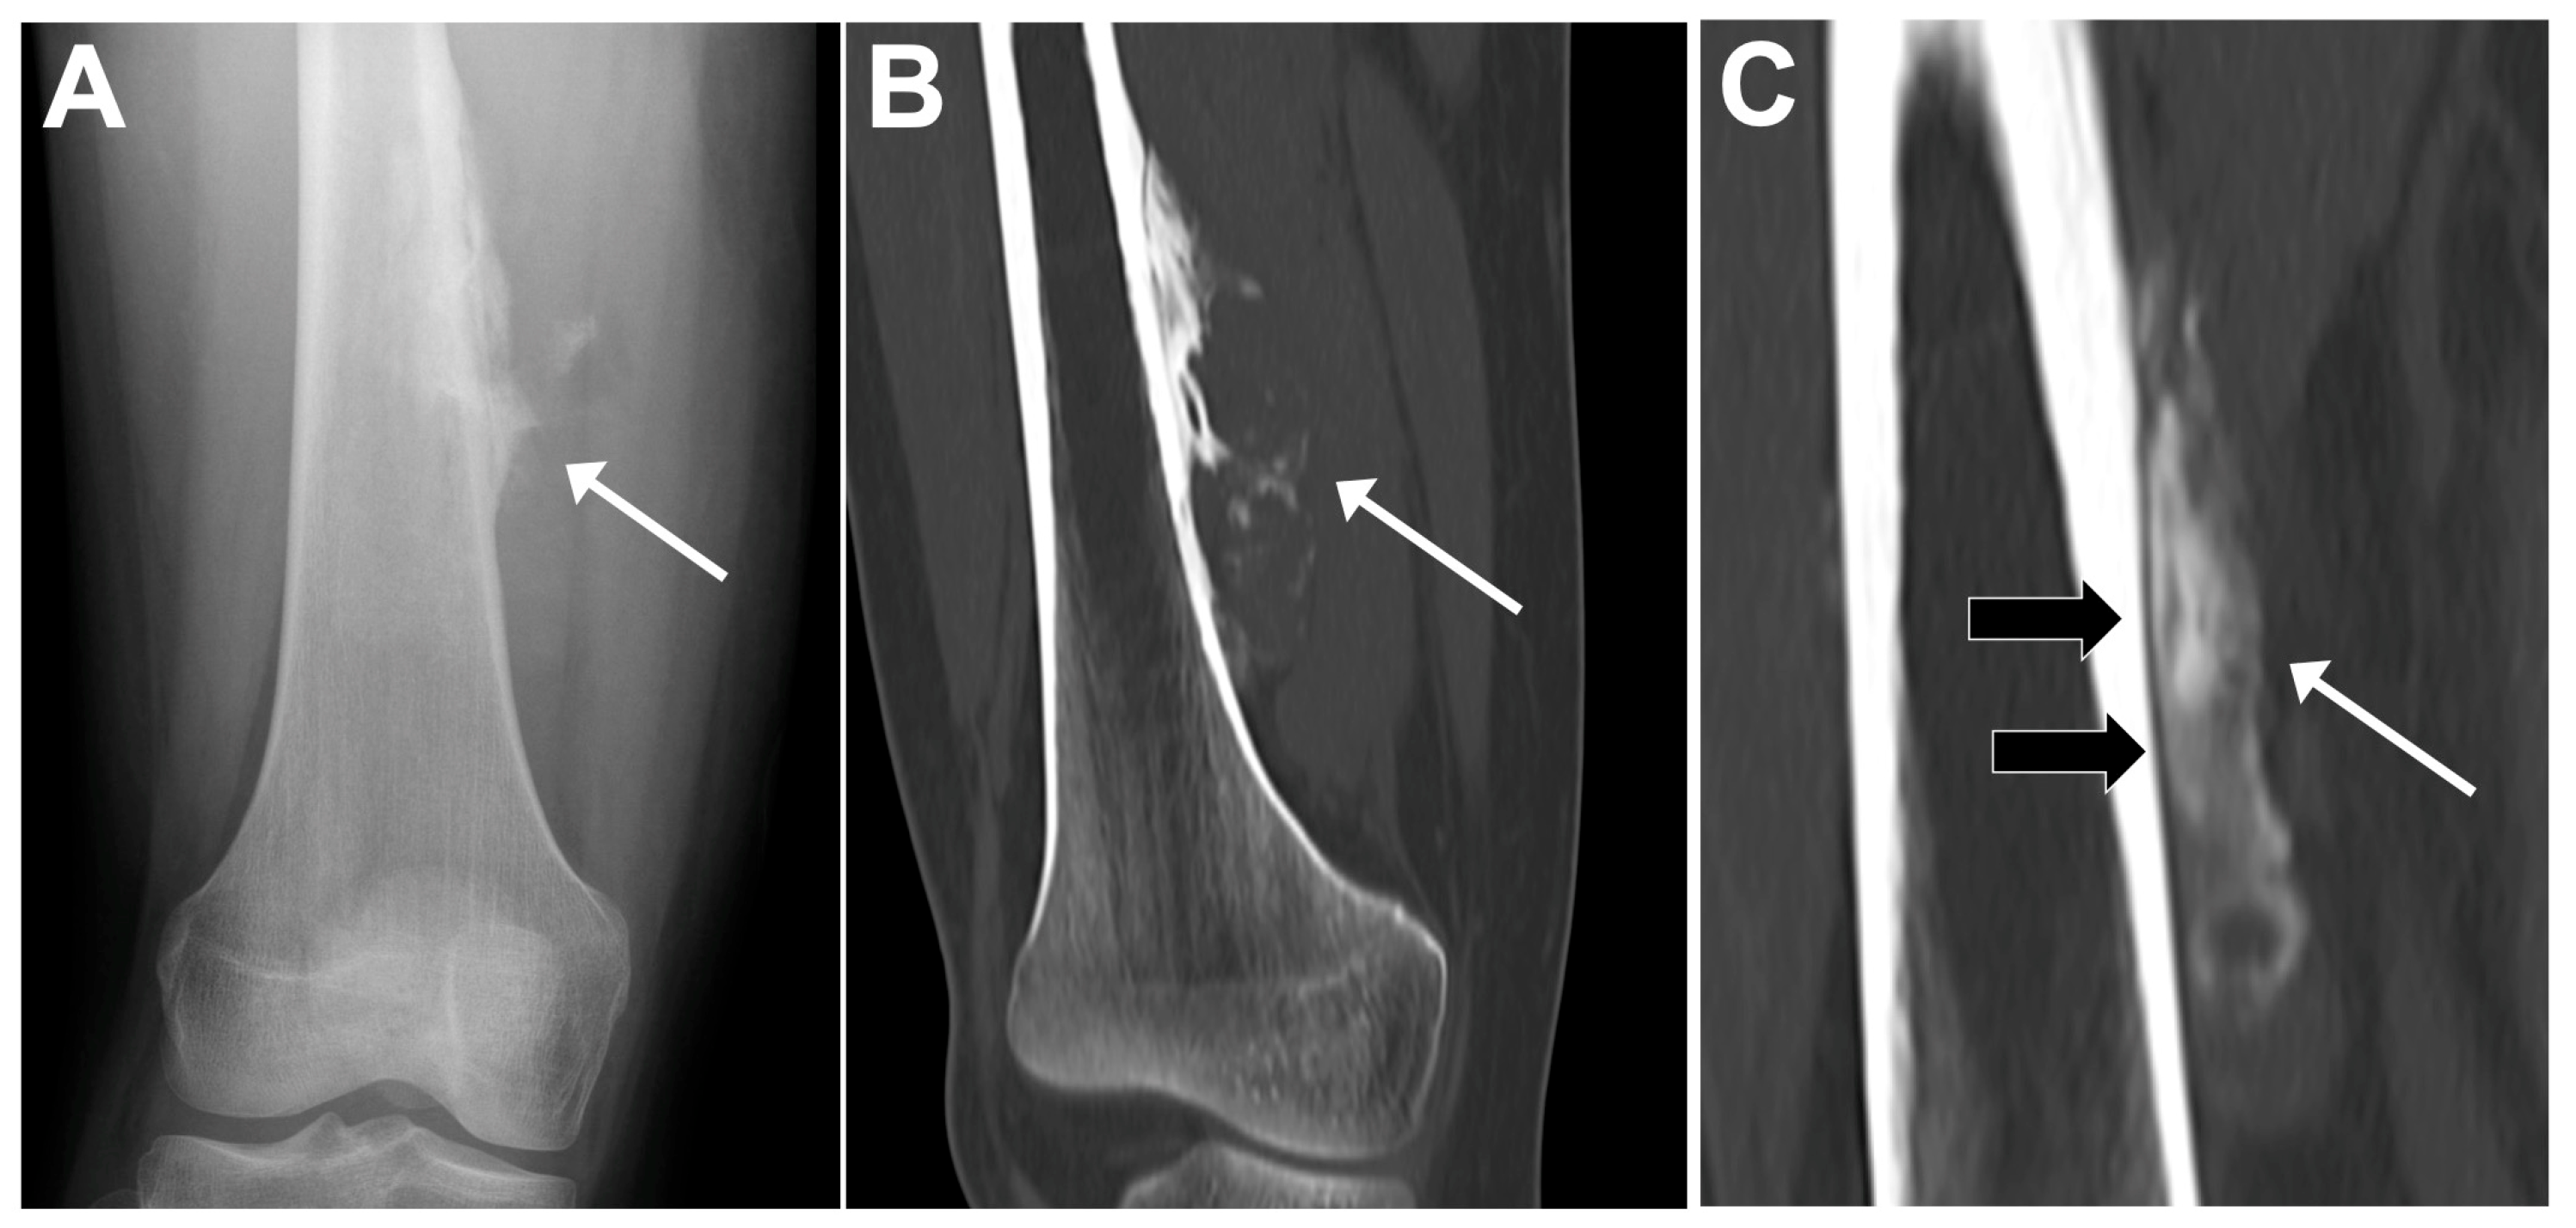

| Conventional osteosarcoma | Mixed (lytic and sclerotic) or completely eburneous | Sunburst, Codman triangle, other irregular/aggressive types | Soft-tissue components frequently displayed |

- Saifuddin, A.; Michelagnoli, M.; Pressney, I. Skip metastases in high-grade intramedullary appendicular osteosarcoma: An indicator of more aggressive disease? Skelet. Radiol. 2021, 50, 2415–2422. [Google Scholar] [CrossRef] [PubMed]